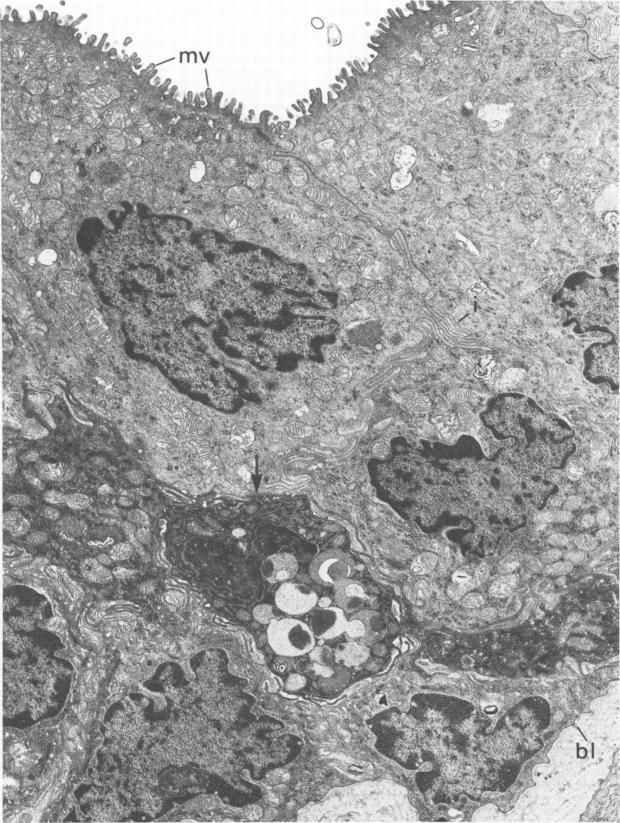

Guinea pig inclusion conjunctivitis, a naturally occurring chlamydial disease of guinea pigs, resolves spontaneously after 3 to 4 weeks. The factors responsible for curbing the infection have not yet been specifically defined. Since Iwata (Invest. Ophthalmol. 15:297-301, 1976) reported cytochemical activity for peroxidase in the conjunctival epithelium of the normal rat, we undertook these studies to determine whether a similar activity exists in the guinea pig, and if so, whether it functions in the elimination of this Chlamydia psittaci infection. Tarsal conjunctivas of 14 normal guinea pigs, 34 infected ones, and 7 control guinea pigs (inoculated with yolk sac only) were excised and tested for peroxidase by the Graham and Karnovsky method (J. Histochem. Cytochem. 14:291-302, 1966). We found that peroxidase activity, virtually absent in normal animals, was intensely stimulated by the infection. This enzymatic activity appeared 2 days after inoculation of the conjunctiva with chlamydia and persisted for 6 to 7 weeks. The enzyme was localized in the rough endoplasmic reticulum and perinuclear cisternae of all layers of the conjunctival epithelium from the external surface to the basal lamina, including cells with no apparent inclusions as well as those heavily parasitized. Reaction in the Golgi complex was variable. No reaction, however, was ever evident in the chlamydial vacuoles or lysosomes, and the organisms continued to grow and multiply during peak enzymatic activity. We therefore concluded that the stimulated enzyme is apparently not directly responsible for the waning of the infection, but instead reflects an alteration of host metabolism that occurs as a consequence of the infection.

豚鼠包涵体结膜炎是豚鼠自然发生的一种衣原体疾病,3至4周后可自发痊愈。抑制感染的因素尚未明确界定。自岩田(《Invest. Ophthalmol.》15:297 - 301,1976年)报道正常大鼠结膜上皮中过氧化物酶具有细胞化学活性以来,我们开展了这些研究,以确定豚鼠是否存在类似活性,若存在,其是否在消除这种鹦鹉热衣原体感染中发挥作用。切除14只正常豚鼠、34只感染豚鼠和7只对照豚鼠(仅接种卵黄囊)的睑结膜,采用格雷厄姆和卡尔诺夫斯基方法(《J. Histochem. Cytochem.》14:291 - 302,1966年)检测过氧化物酶。我们发现,正常动物几乎不存在的过氧化物酶活性在感染后受到强烈刺激。这种酶活性在结膜接种衣原体后2天出现,并持续6至7周。该酶定位于从外表面到基底层的结膜上皮各层的粗面内质网和核周池,包括无明显包涵体的细胞以及严重寄生的细胞。高尔基体中的反应各不相同。然而,衣原体空泡或溶酶体中从未出现明显反应,并且在酶活性高峰期病原体继续生长繁殖。因此,我们得出结论,受刺激的酶显然不是感染减弱的直接原因,而是反映了感染导致的宿主代谢改变。